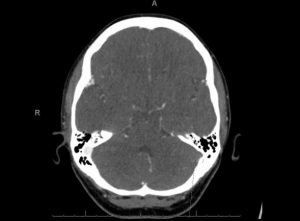

Este trastorno provoca coágulos de sangre en las venas del cerebro, y también da un recuento de plaquetas muy bajo.

Los dolores de cabeza lejos de irse empeoraron, llegando a mareos y sensibilidad a la luz llevándola a hospitalización 12 días después.

Se le diagnostico VITT y la trataron con bivalirudina, un anticoagulante, luego de esto su recuento de plaquetas aumentó, el dolor de cabeza y los coágulos desaparecieron, dándola de alta seis días después.